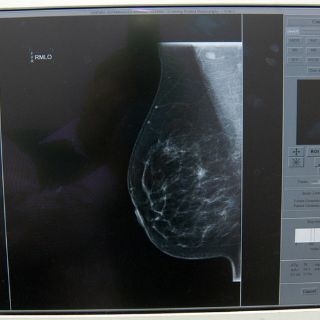

Detalló que en la actualidad el IMSS cuenta con acciones específicas para la prevención, la detección y el control de ese padecimiento, como son la promoción a la salud.

La autoexploración mamaria cada mes, a partir de los 20 años y hasta los 69 años de edad, sin omitir la revisión clínica de la glándula mamaria de los 25 a los 69 años y la mastografía cada dos años de los 50 a los 69 años, aunque se aconseja desde los 40 años, en caso de antecedentes familiares de este mal.